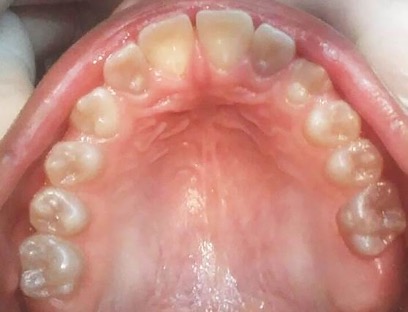

En la radiografía panorámica de control del año 2015 se observó la progresiva obliteración del conducto radicular en el grupo incisivo superior e inferior y en los primeros molares permanentes; presentado los premolares en erupción, un conducto radicular anormalmente amplio en toda su longitud (Figura 8). En la del año 2018 se visualizó la continua aposición de dentina a nivel radicular que obliteró en forma casi total los conductos de la mayoría de las piezas dentarias, a excepción de los segundos molares inferiores (Figura 10).

Figura 10: Rx panorámica 2018.

Figura 11: Controles clínicos 2018

En el último control realizado en el año 2018 (Figura 11) el paciente mantuvo el estado de salud logrado. El análisis cariogénico fue moderado (por su historia pasada de caries y su condición biológica específica) y el gingivoperiodontal bajo. El paciente continúa en atención en la COIN. Fue derivado en varias oportunidades al servicio de Ortodoncia de la Facultad de Odontología de la Universidad de Buenos Aires, pero hasta el momento no encaró ningún tratamiento propuesto.